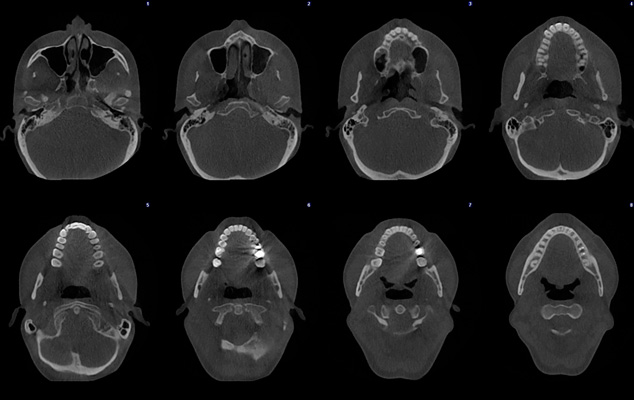

Ultra Low dose image - Full skull

Planmeca ProMax 3D Mid - FOV Ø 200 x 170 mm. - Voxel size 300 µm / 600 µm - Effective patient dose 14.7 µSv

Planmeca ProMax 3D Mid - FOV Ø 200 x 170 mm. - Voxel size 300 µm / 600 µm - Effective patient dose 14.7 µSv

Planmeca ProMax 3D Classic - FOV Ø 40 x 50 mm. - Voxel size 150 µm - Effective patient dose 14.4 µSv

Ultra low dose image - Orthodontic case

Planmeca ProMax 3D - FOV Ø 85 x 50 mm. - Voxel size 400 µm - Effective patient dose 7.9 µSv

Ultra low dose image - Orthodontic case

Planmeca ProMax 3D - FOV Ø 85 x 50 mm. - Voxel size 400 µm - Effective patient dose 4.0 µSv